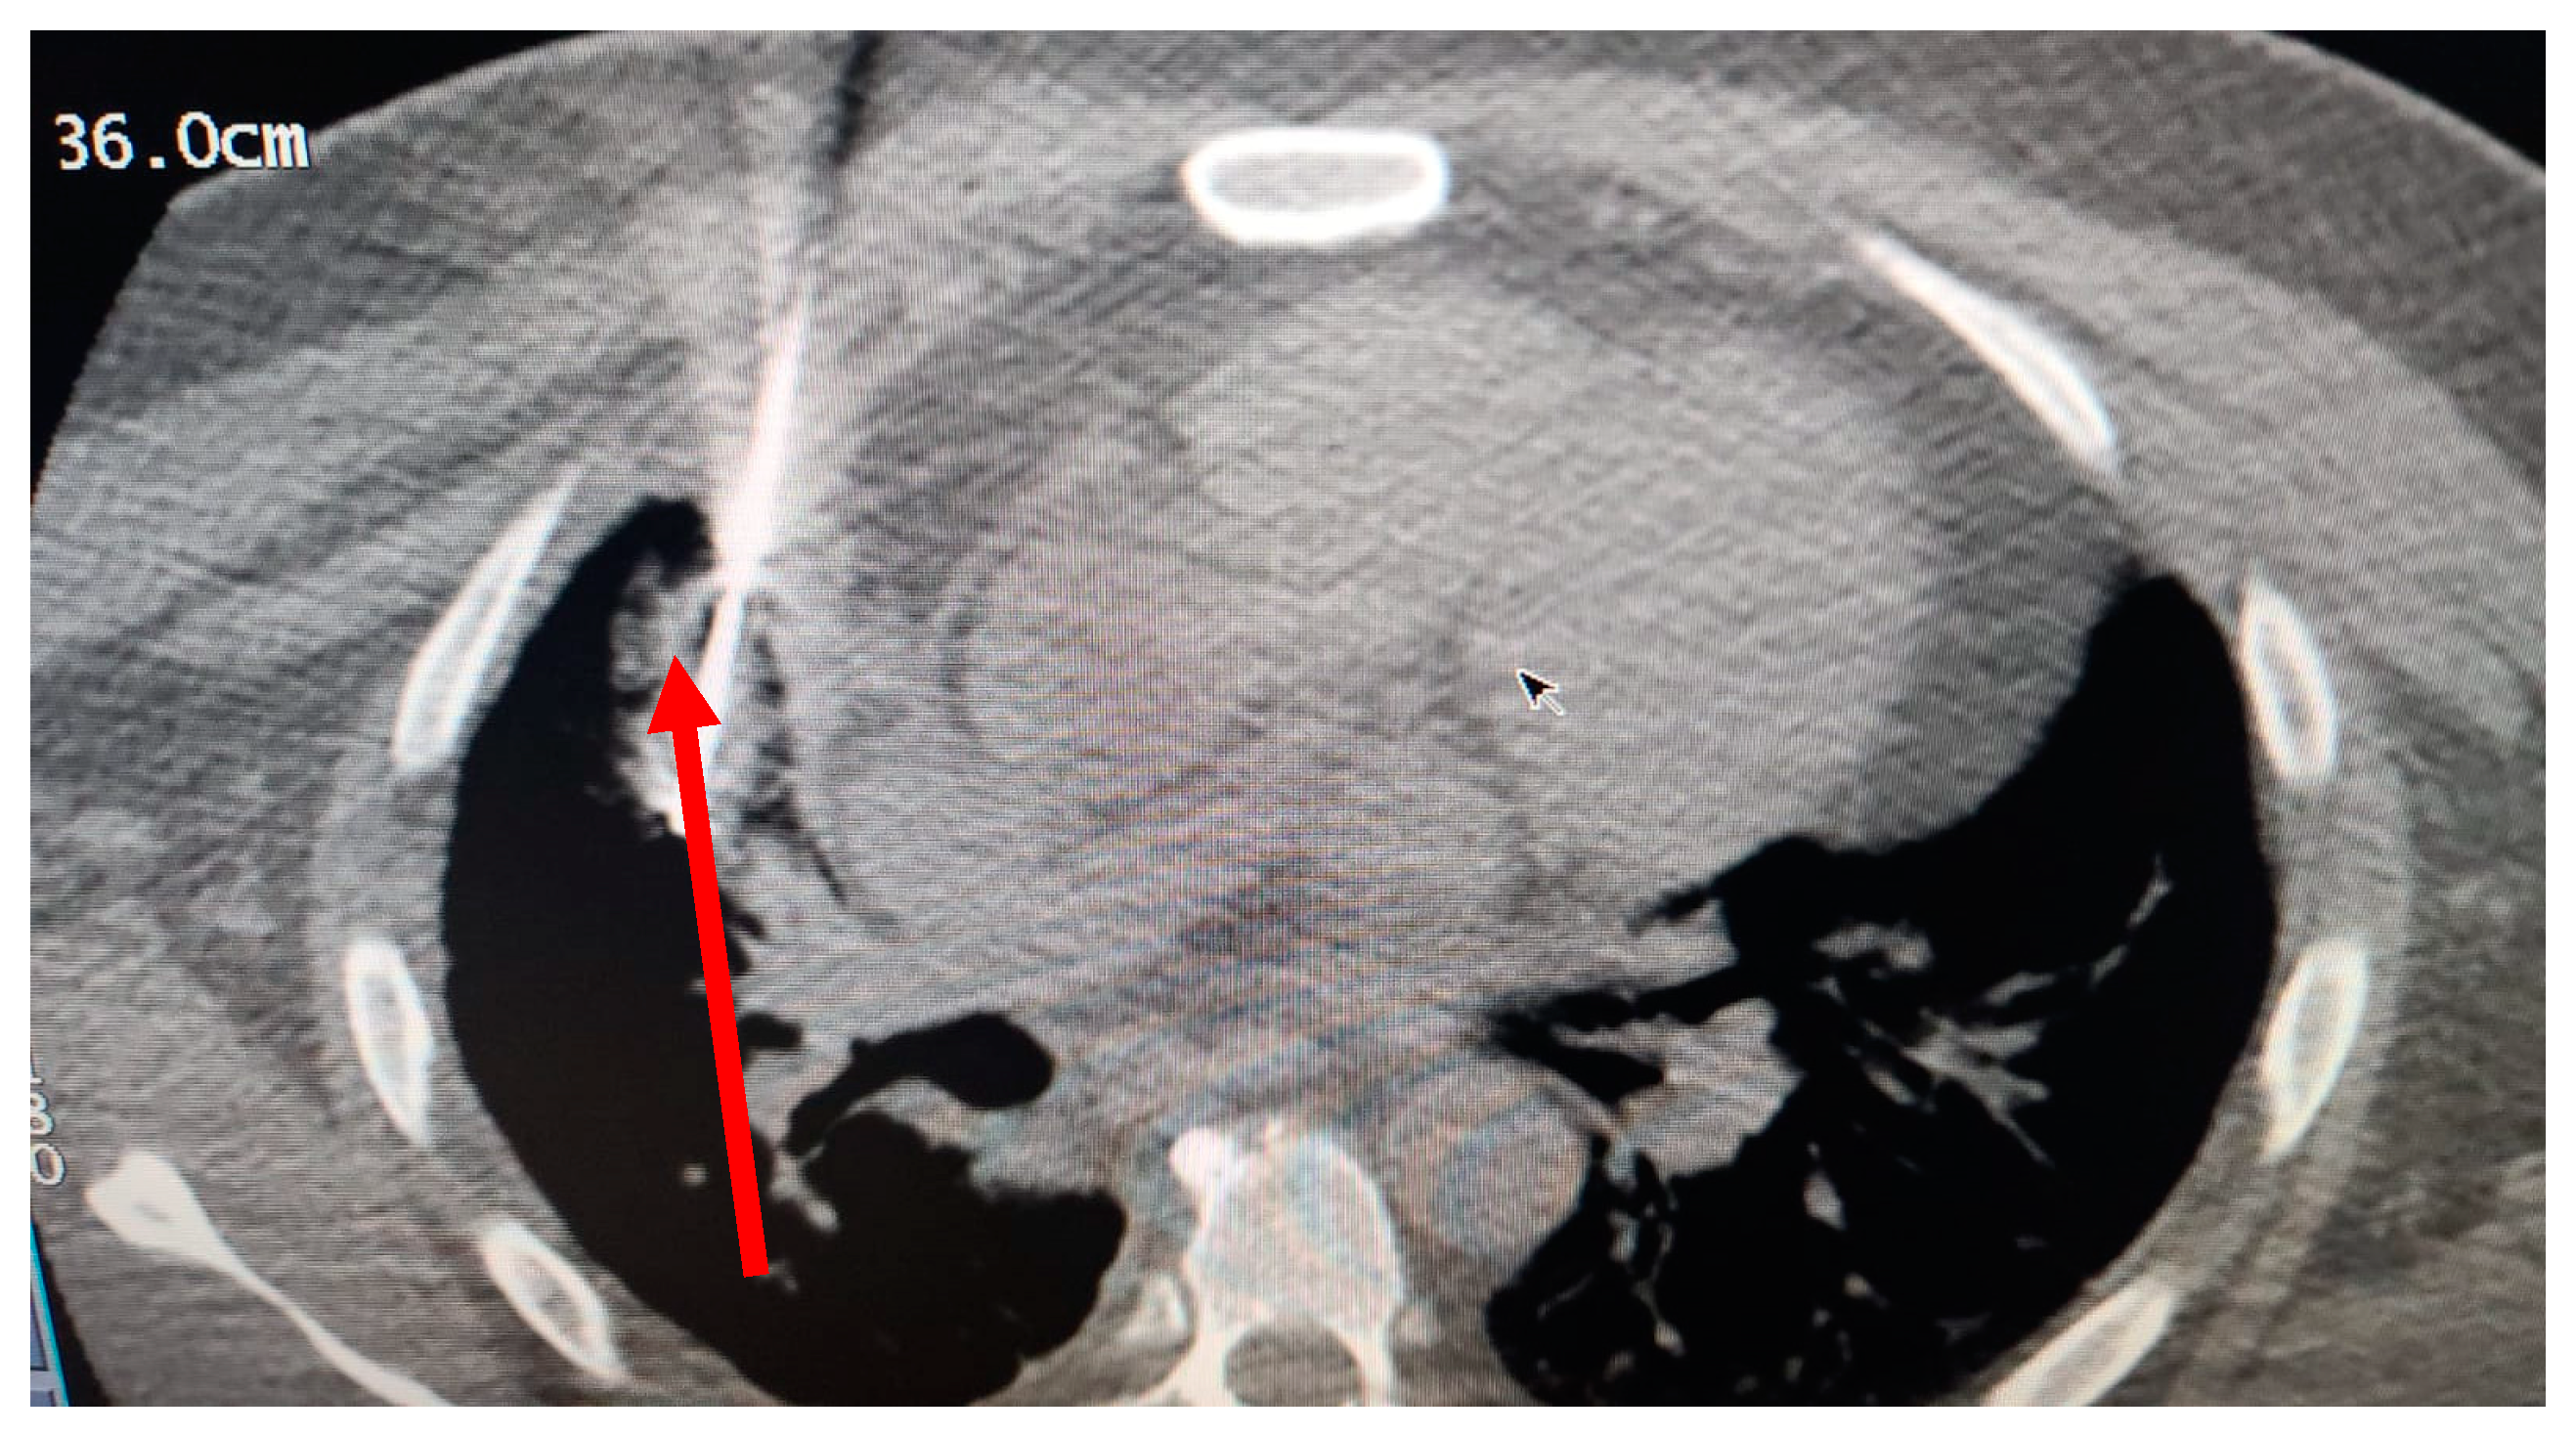

In October 2018, a 24-year-old patient arrived at our cryosurgery unit with the results of a CT scan. The presence of bilateral pulmonary and mediastinal lymph node metastases close to the esophagus was highlighted (Figure 6).

Figure 6. CT scan images indicate the presence of bilateral pulmonary and mediastinal lymph node metastases close to the esophagus. The arrow indicates the tumor’s location.